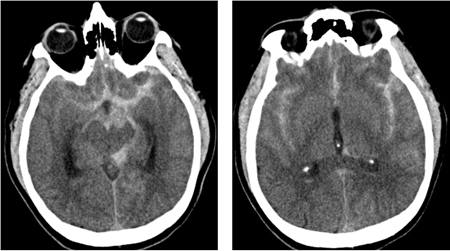

Subarachnoid hemorrhage

CT brain showing subarachnoid hemorrhage from a ruptured posterior cerebral artery aneurysm (2 of 2)

Courtesy of Dr Salah Keyrouz; used with permission

Communicating hydrocephalus in the setting of subarachnoid hemorrhage; note dilation of fourth and temporal horns of lateral ventricles